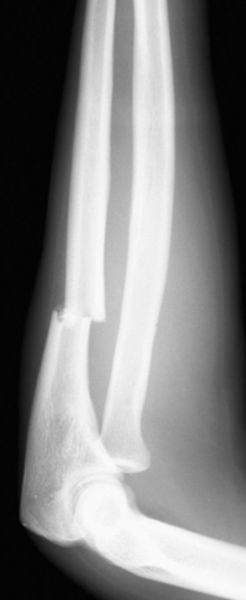

孟氏骨折

尺骨骨折

桡骨头脱位